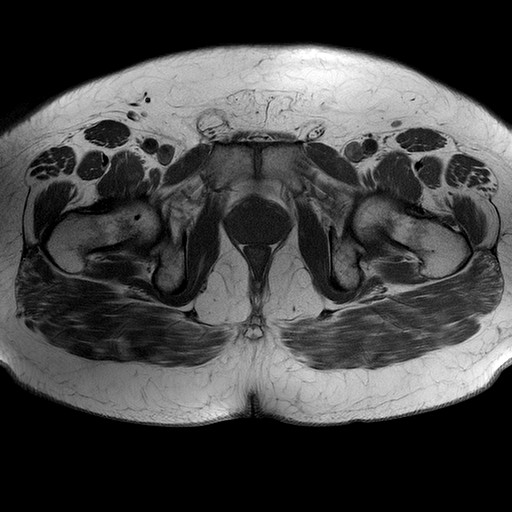

Esami: RMN BACINO

T1W_TSE

Evidenti e simmetriche alterazioni osteofitosiche in regione coxo femorale con riduzione delle rime articolari. Degenerazione completa del cercine glenoideo. Non attuali segni di versamento articolare. Non segni di edema osseo che escludono attuale algodistrofia od osteonecrosi. Lieve e simmetrica riduzione del trofismo della muscolatura glutea.